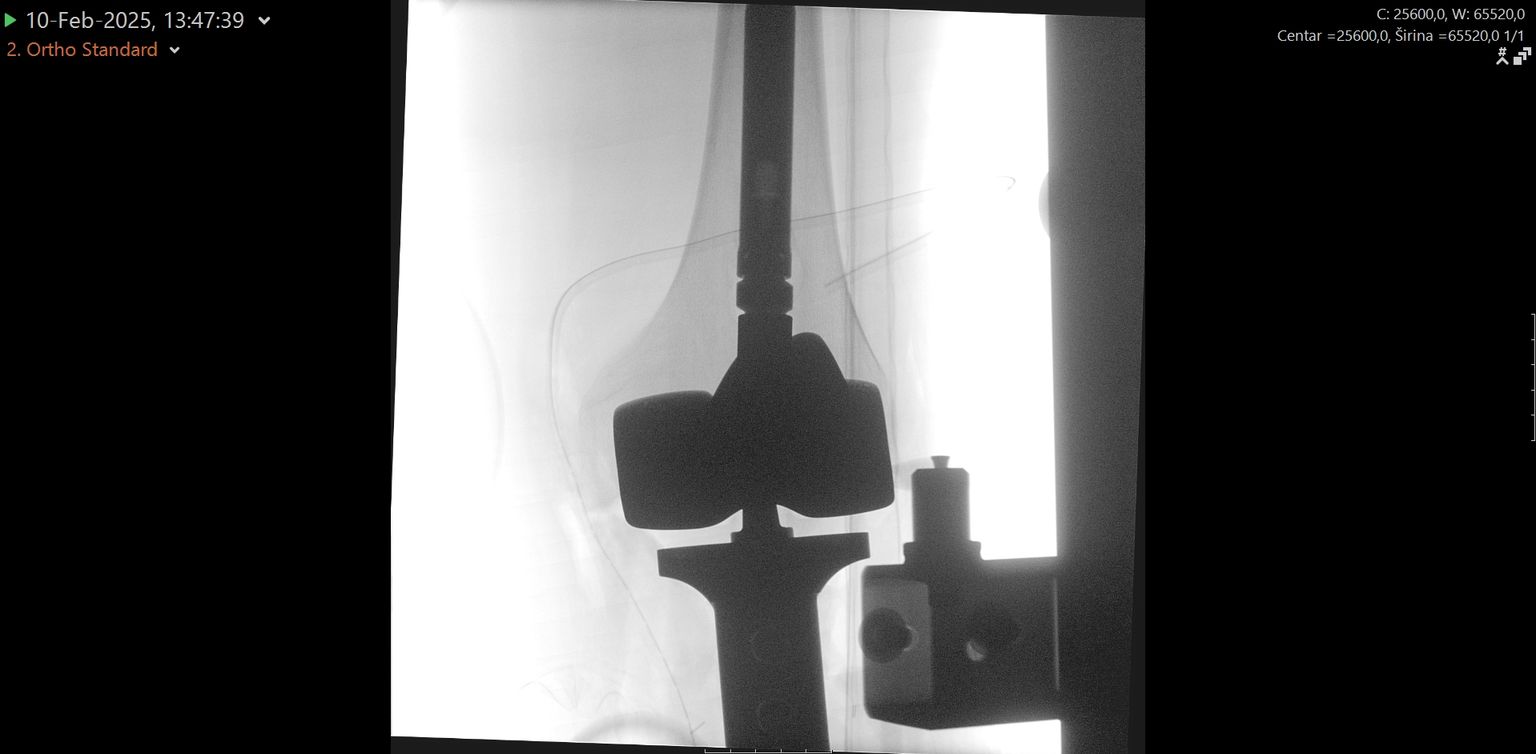

• Zahvat u KBC-u Split - 5 Foto: KBC Split

• Zahvat u KBC-u Split - 2 Foto: KBC Split